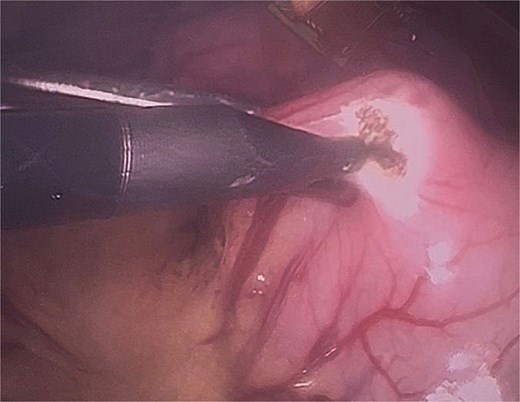

Twelve hours later, she was evaluated by the new emergency surgery team, who found a complete upper obstruction with a foreign body occupying the lower esophagus, the entire stomach, and the entire duodenum (Figs 1–3). A diagnostic laparoscopy (Fig. 10) with gastrotomy was performed (Figs 4 and 5), including foreign body removal (Figs 6 and 7), gastric repair (Fig. 8), and placement of a tubular drain. The findings revealed a large foreign body containing a significant amount of malodorous hair, measuring 30 cm long and 12 cm wide (Fig. 9). Large gauze pads were placed around the stomach to prevent contamination, and the bezoar was removed first through the duodenal area, as this was the area of smallest diameter and least compression. The gastric and esophageal portions were then removed. The foreign body was extracted transumbilically through a small 6 cm incision, protecting the abdominal wall with an isolation device. Gastric repair was performed using a 3–0 continuous suture polydioxanone (PDS) in a single layer. The cavity was irrigated with 3 l of saline solution. The operation was 2 h. Postoperative management included a nasogastric tube on gravity drainage, intravenous piperacillin/tazobactam 4.5 g every 6 h, intravenous tramadol 100 mg every 8 h for analgesia, and intravenous dimenhydrinate 50 mg every 8 h. The patient progressed favorably, with oral intake initiated on postoperative day 4. The tubular drain was removed on day 5 with minimal serous output. Psychiatry discovered that the patient had been diagnosed with trichotillomania in 2014 but refused pharmacological treatment. The patient confirmed that she has suffered from trichophagia since the age of 14. Pharmacological treatment with psychotropic medications and psychological support was initiated. On day 7, the patient was on a soft diet, without a nasogastric tube, with a white blood cell count of 10 740 cells/μl and 0% band neutrophils. Treatment with clomipramine was initiated. She was discharged that day and evaluated 7 days later with no problems.

Initial gastrotomy beginning at the antral region and extending longitudinally toward the pylorus (without compromising it).

Identification of the bezoar after gastrotomy, revealing a large amount of contaminated trichobezoar material.

In our technique, we emphasize the strategic placement of gauze around the gastric incision to prevent the bezoar from contacting and contaminating the abdominal cavity. We also developed a method that enables removal of the bezoar without necessitating a large gastric incision, optimizing the advantages of a minimally invasive approach.